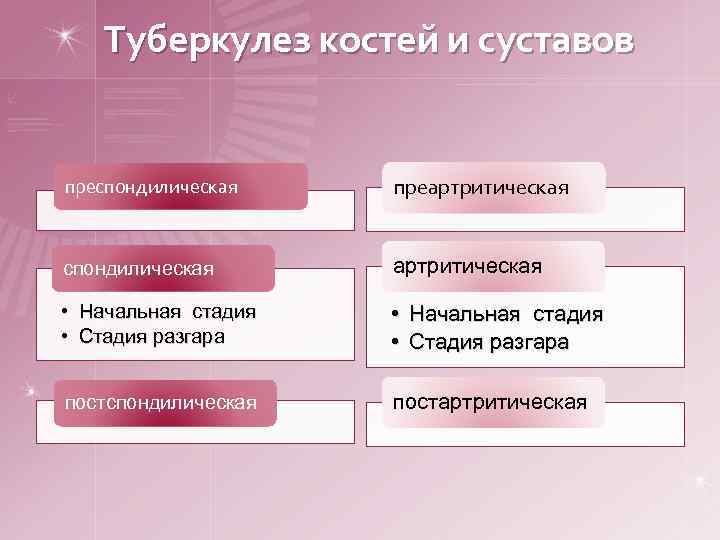

Туберкулез костей и суставов преспондилическая преартритическая спондилическая артритическая • Начальная стадия • Стадия разгара постспондилическая постартритическая